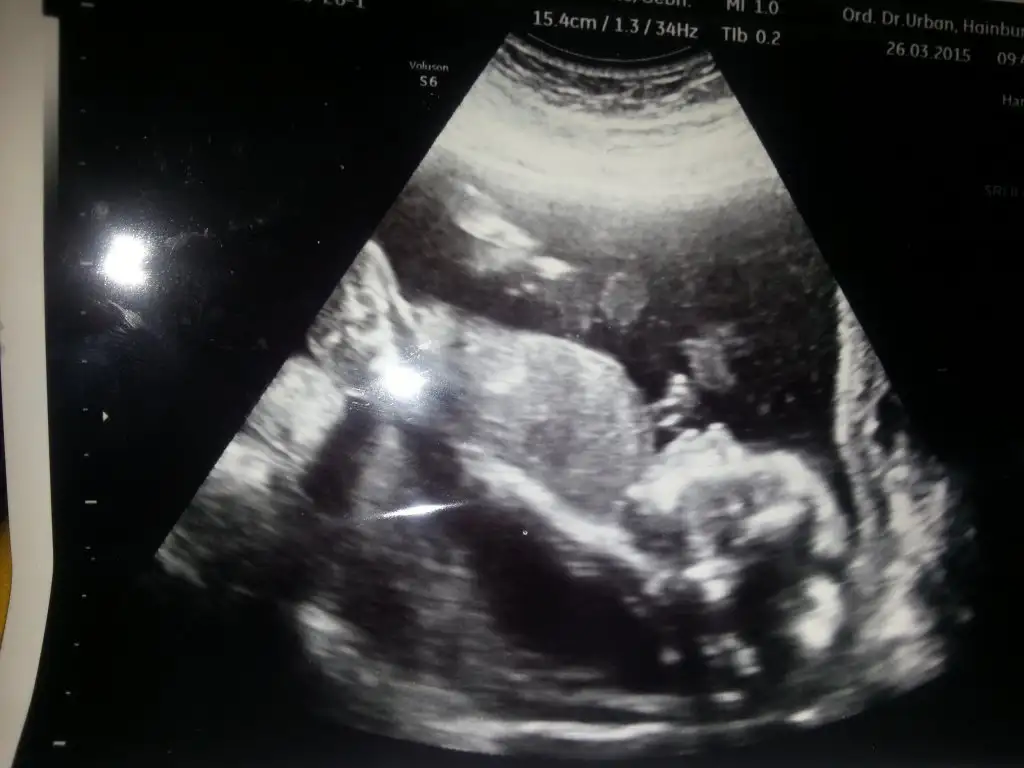

dr soylemeden siz gorun genital nub teorisi ( bebegin cinsiyeti)

Kizlarr bebis donmus bakinsana ama goremedim diyo bukezde tam bi rezalet 19+3 ciktik nirmalde bugun 18 olmustu nolur siz bari yorumlayin :(((

Kizlarr bebis donmus bakinsana ama goremedim diyo bukezde tam bi rezalet 19+3 ciktik nirmalde bugun 18 olmustu nolur siz bari yorumlayin :KK43:((

Canim doktor kiza veya erkege benziyor demedimi hic neredeyse 4 bucuk aylik 12. Haftalik nubundan belli olmadimi peki? Canim dopplere giriliyor ya 20. Haftada kesin gorunur damarlarini bile incelemislerdi oglumun hic bi testi yaptirmadim ama dopplere girdim hemde cok guzel bir ani kaldi elimde kesinlikle girmeni tavsiye ederim :))

bir de kızlar, akşam oğlumun ultrason fotolarını buldum, yahu bizim oğlanın nubu bildiğiniz kızmışşş:KK57: bunda da nubu direk erkek bakalım ne çıkacak bahtımıza:KK70: